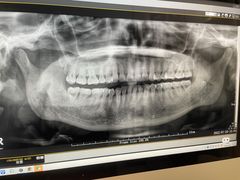

• -牙博士口腔品牌连锁(杨浦店)

闪闪 | 22-07-28

报错